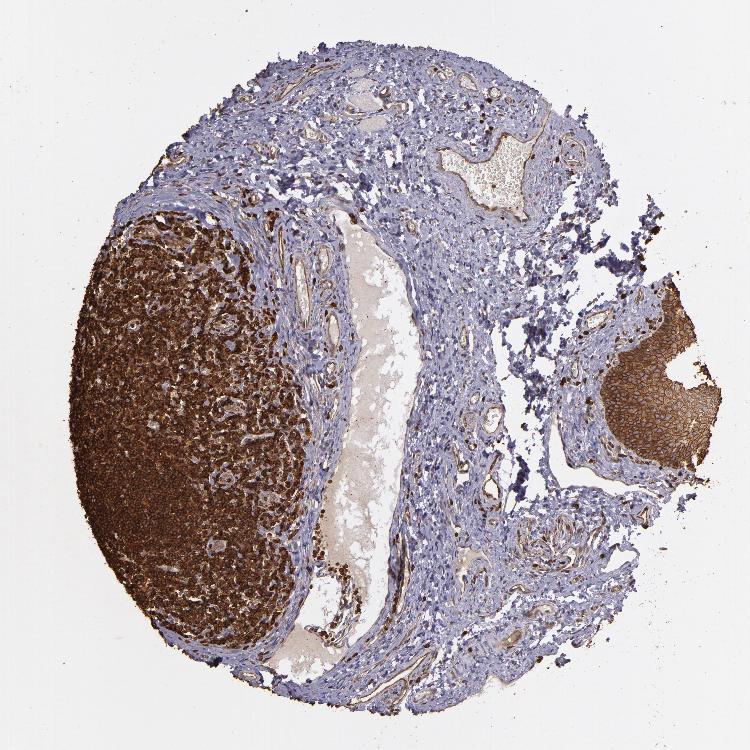

TISSUE PRIMARY DATA ORAL MUCOSA Show tissue menu

Oral mucosa

ORAL MUCOSA - Antibody stainingi

Antibody staining in the annotated cell types in the current human tissue is reported as not detected, low, medium, or high, based on conventional immunohistochemistry profiling in selected tissues. This score is based on the combination of the staining intensity and fraction of stained cells.

Each image is clickable and will lead to virtual microscopy that enables deeper exploration of all samples and also displays staining intensity scores, fraction scores and subcellular localization as well as patient and tissue information for each sample.

Antibody HPA009672Antibody HPA027247Antibody CAB001962

Squamous epithelial cells MediumMediumHigh